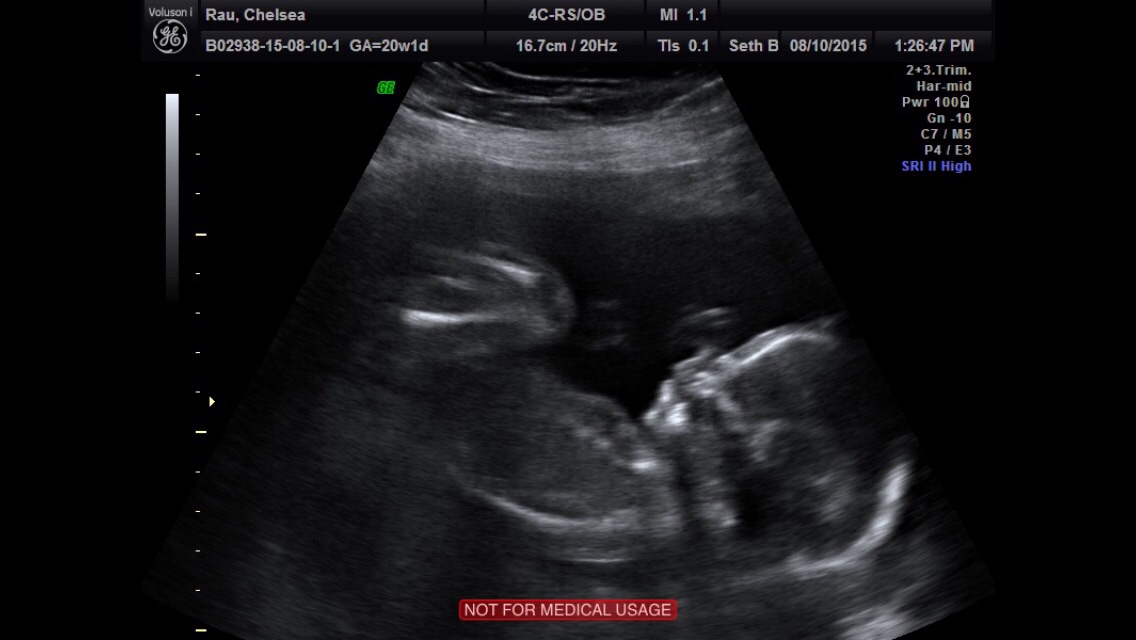

• Here's some awesome pics!

I had an anatomy scan with my high risk doctor at 17.5 weeks and my reg anatomy scan with my reg doctor at 20 weeks this past Thursday.

Perfection so far!

• Just had my Anatomy scan this past Tuesday (8/4/15 - 20.0 weeks). So far, so good! Today I am 20.3 weeks.